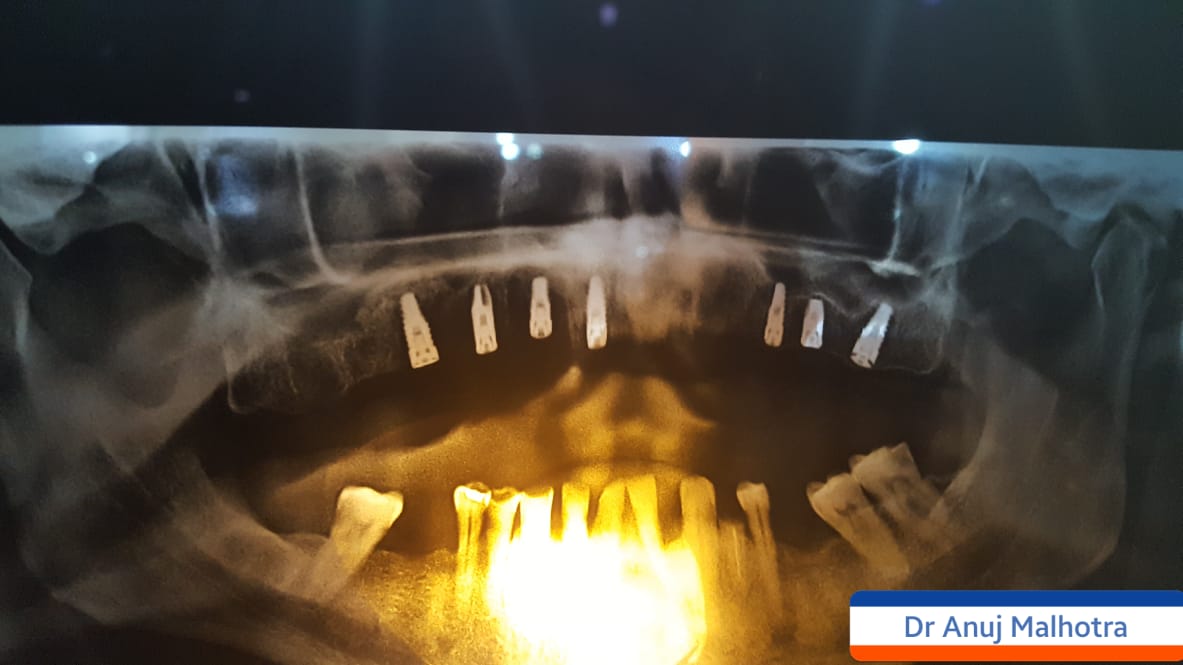

Full Mouth Implant Case